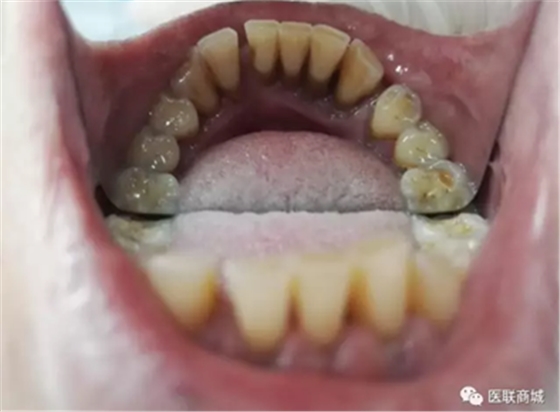

該患者本身就有慢性牙周炎,加上高血壓的基礎(chǔ)疾病,長(zhǎng)期服用硝苯地平,這個(gè)是導(dǎo)致藥物性牙齦增生常見(jiàn)藥物之一,針對(duì)這樣的患者在牙周基礎(chǔ)治療時(shí)必要的,但在基礎(chǔ)治療的同時(shí),一定要建議患者更改降壓藥物,同時(shí)必要時(shí)手術(shù)切除增生牙齦,可以達(dá)到很好的效果,見(jiàn)圖片(圖中白色為雙氧水沖洗后效果)。